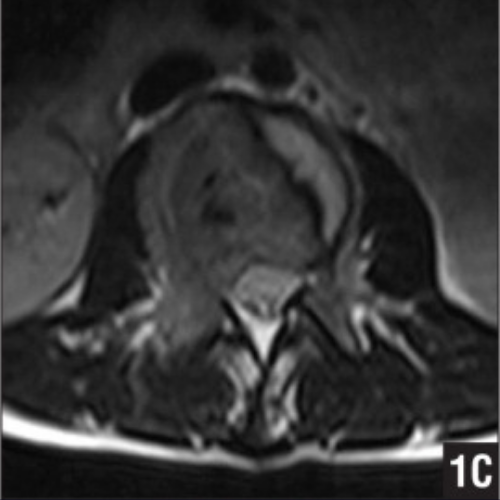

Tanı aşamasında en güçlü araç kontrastlı MR (Emar) görüntülemesidir. Kemik yapının detaylı incelenmesi için Bilgisayarlı Tomografi (BT) ve tümörün yayılımını belirlemek için PET/CT gibi yöntemler kullanılır. Kesin teşhis ise genellikle doku örneği (biyopsi) ile konulur.

Tedavi yaklaşımı; tümörün tipine, büyüklüğüne, konumuna ve hastanın genel sağlık durumuna göre multidisipliner bir ekip (beyin cerrahı, onkolog, radyolog) tarafından belirlenir. İyi huylu (benign) tümörlerde sadece cerrahi çıkarma yeterli olabilirken, kötü huylu (malign) tümörlerde cerrahiye ek olarak radyoterapi ve kemoterapi uygulanır. Günümüzde "Stereotaktik Radyocerrahi" (CyberKnife gibi) yöntemleri, cerrahinin riskli olduğu bölgelerdeki tümörlere yüksek dozda radyasyonu hassas bir şekilde odaklayarak başarılı sonuçlar vermektedir.